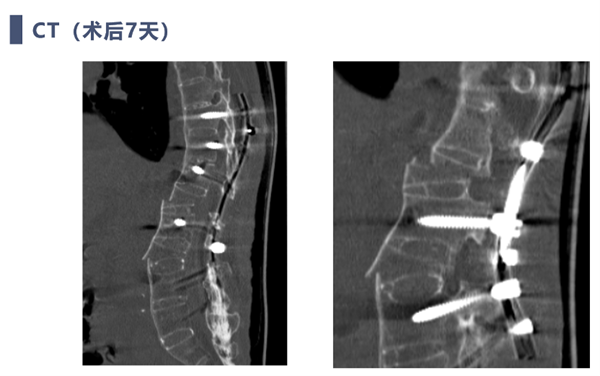

术后复查

强直性脊柱炎后凸矫形手术患者脊柱自我代偿能力基本丢失,术前需要精确的评估及手术计划来确保患者术后平视,坐立,平卧等基本需求。

本例患者重度营养不良,体重只有35公斤,需要严格控制出血量,本例患者采用显微镜辅助双节段COWO截骨,出血少,矫形效果良好。

对于强柱患者矫形过程需要防止ST(矢状位移)发生,避免脊髓损伤,本例患者采用保留部分骨连接,交叉上棒与体位复位相结合方式,复位过程安全平稳,无脊髓损伤发生。